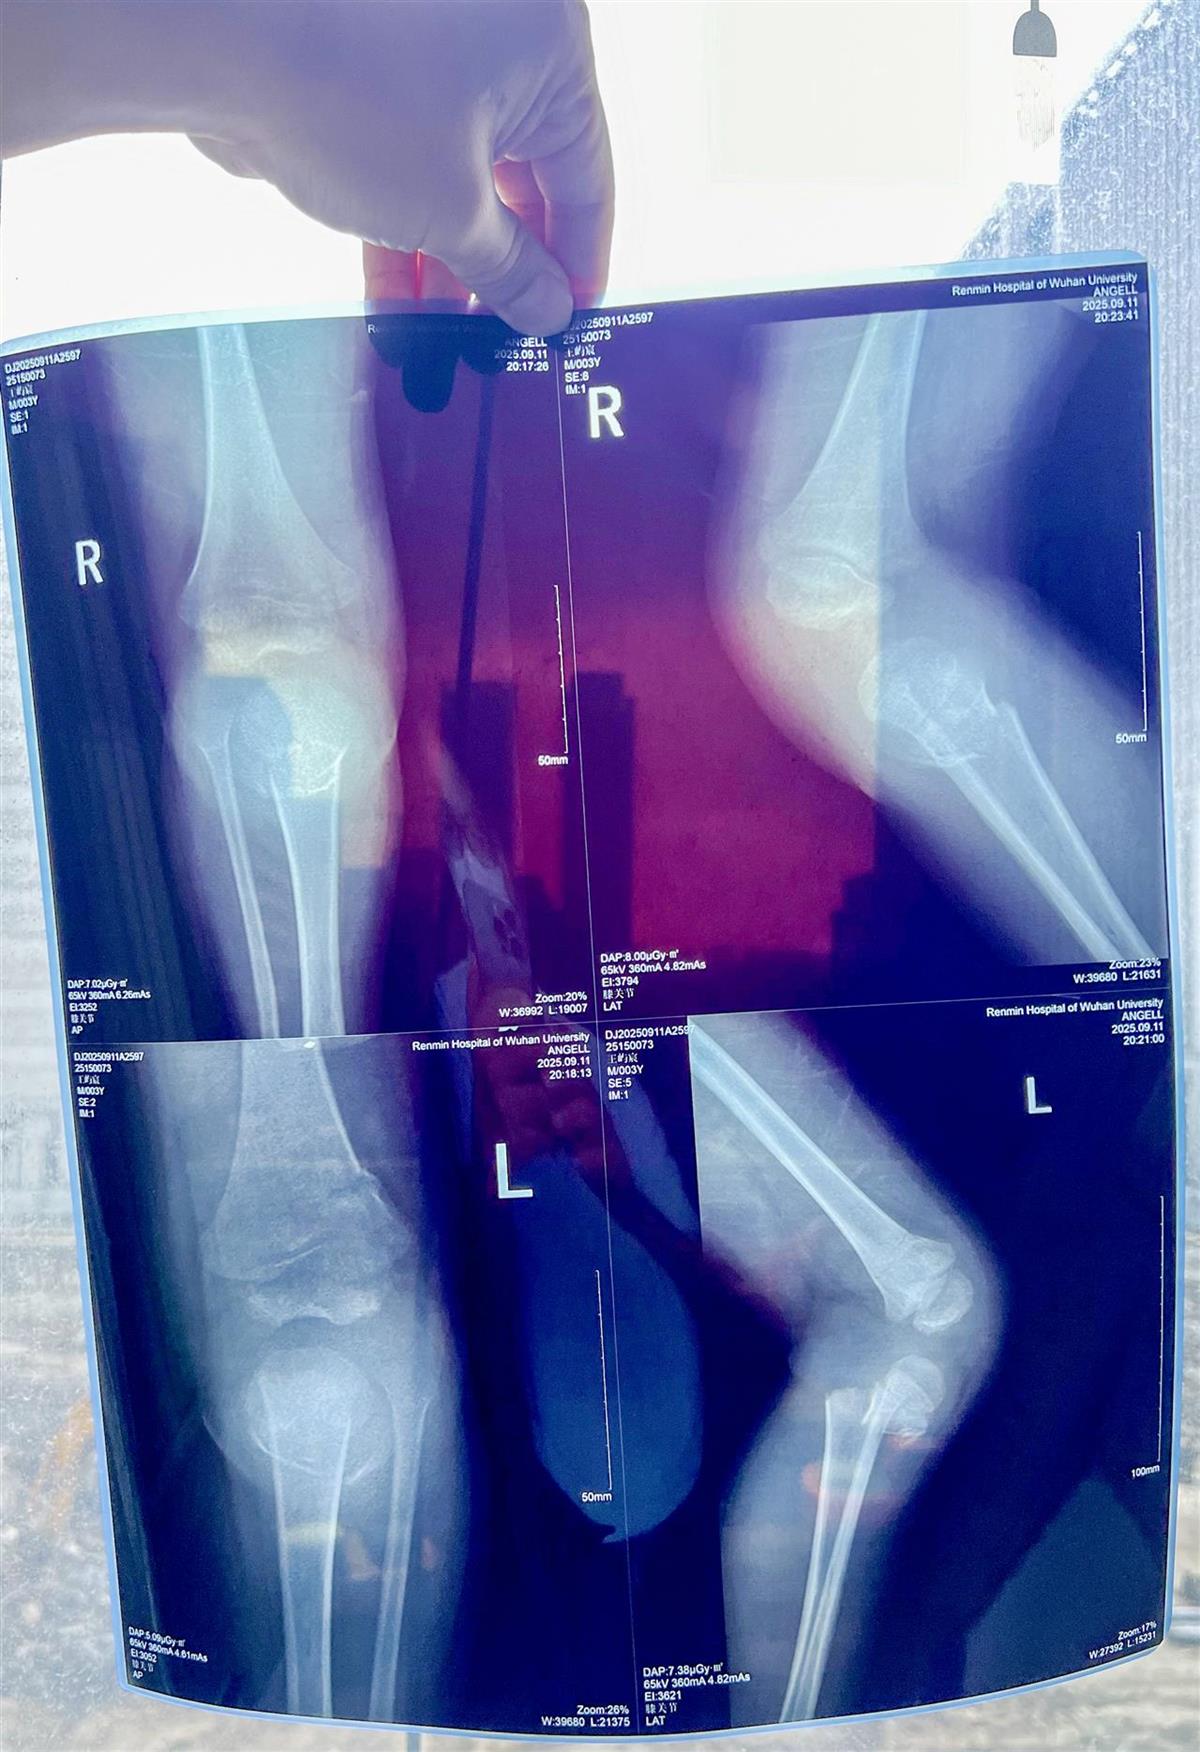

经医院检查,小墨墨的伤情不容乐观:不仅存在颅内出血,左侧股骨下段骨质中断、不连续,左、右侧胫骨近段也出现骨质中断、不连续的情况,且断端存在错位。

检查发现孩子多处骨折